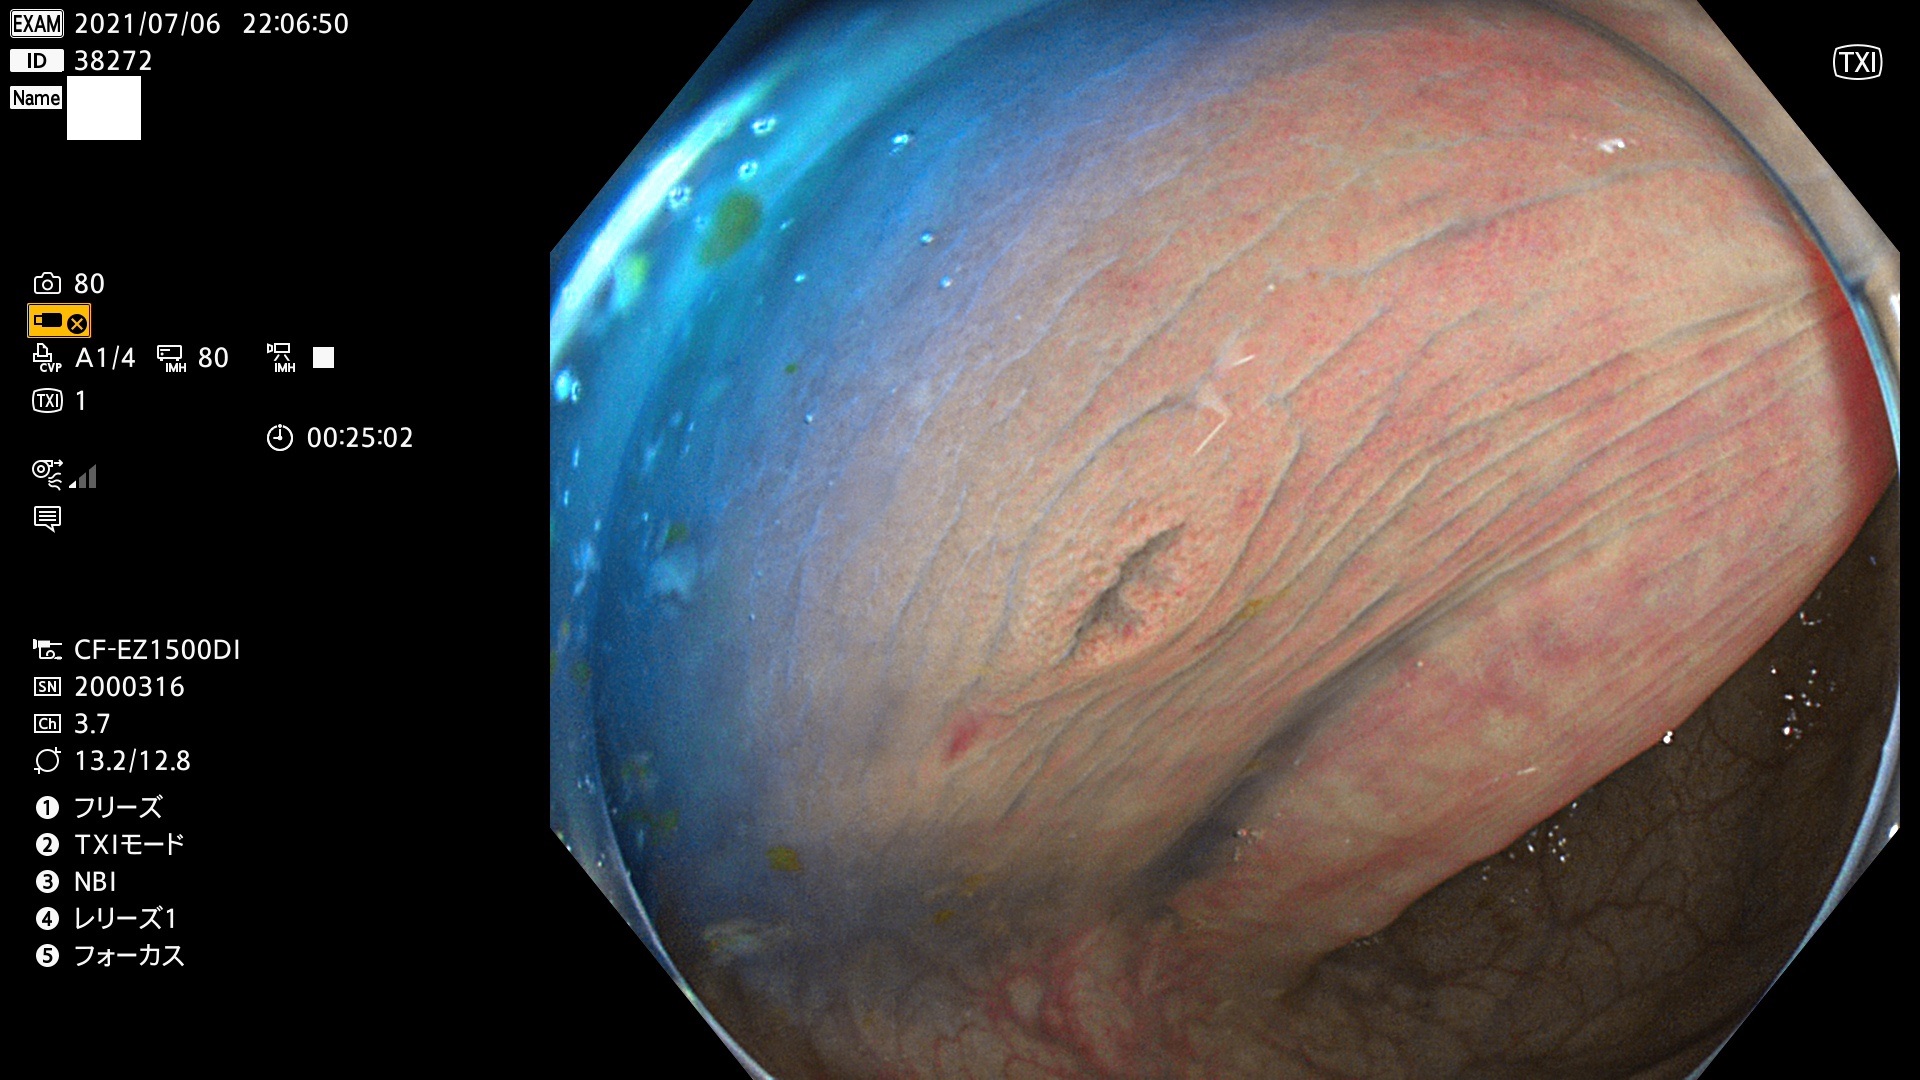

発見困難で危険性の高い平坦型病変(上記100名より抽出)